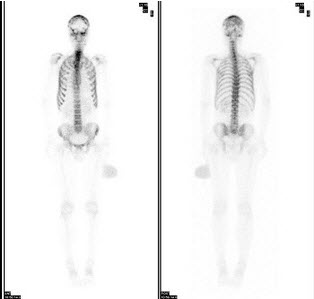

103、多项选择题

男性,62岁,膀胱印戒细胞癌术后半年,全身酸痛,对骨显像地描述正确的是()

A.颅骨多个“轮圈征”,提示有溶骨性病变

B.脊柱骨、肋骨弥漫性均匀性浓聚,肾脏不显影,是“超级骨显像”

C.提示中轴骨广泛转移癌

D.该患者预后不良

E.以上都不是

点击查看答案